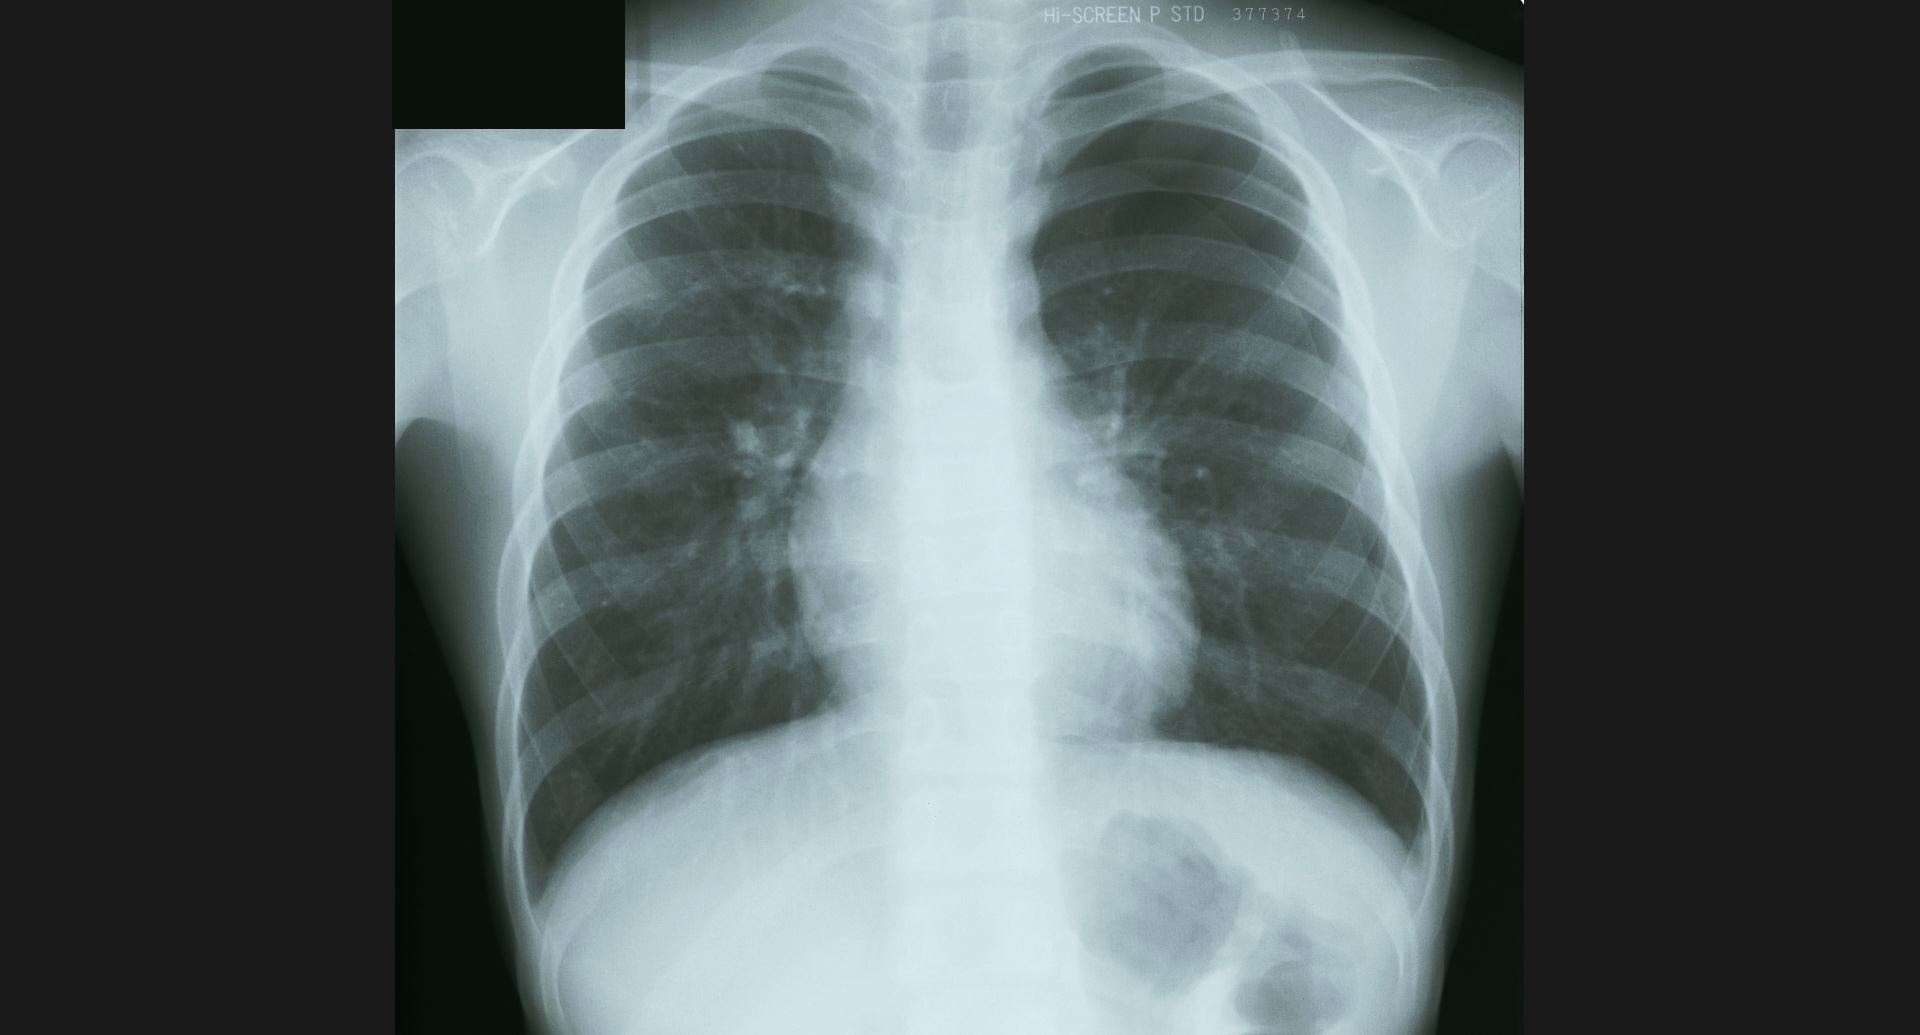

fig.9(94KB) :Pneumoconiosis

細かい斑状陰影。